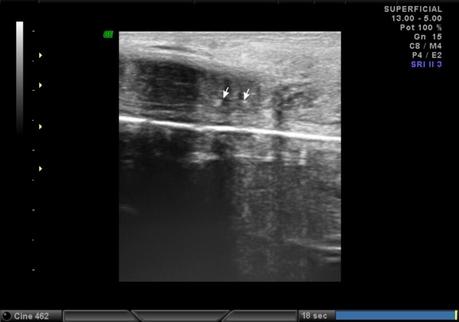

A nivel de base del pené, entre los cuerpos cavernoso y esponjoso en su porción central se observa la presencia de calcificación, que mide 2.2 mm. En tercio distal del pené, a nivel de cuerpos cavernosos con presencia de calcificación que mide 1.8 mm.

A NIVEL DE BASE Y TERCIO DISTAL DEL PENÉ, EN CUERPOS CAVERNOSOS CON PLACAS A RELACIÓN A ENFERMEDAD PEYRONIE.